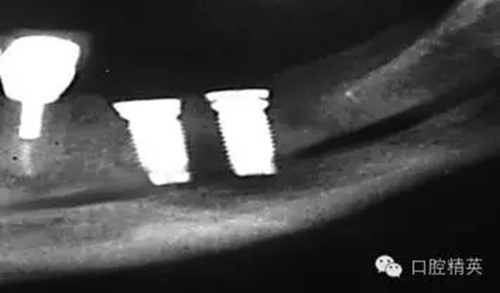

圖4:兩維曲面斷層影像難以獲得精確定位,有的醫(yī)生為了避免損傷下頜神經(jīng)管而應用短種植體。這樣做的結果是增加了修復體-種植體長度比,隨著時間的流逝會造成骨吸收,最終可能導致種植體折斷。骨內折斷的種植體片斷需要手術取出,然后進行植骨,骨質愈合后再次種植,這些步驟不僅創(chuàng)傷大,而其從心理和經(jīng)濟上都會對患者造成損失。

如這個病例展示的,CBCT斷層掃描揭示了牙槽骨根方的凹陷。這樣就避免了術中的意外,醫(yī)生可以在術前完善的計劃,向患者交代清楚手術方法、風險、以及植骨所需增加的相應費用等問題。在兩維的放射影像中是無法預先觀察到這個問題的。僅使用兩維放射診斷帶來的另一個并發(fā)癥是種植體折斷。(圖4)前面提過,兩維曲面斷層影像難以獲得精確定位,有的醫(yī)生為了避免損傷下頜神經(jīng)管而應用短種植體。這樣做的結果是增加了修復體-種植體長度比,隨著時間的流逝會造成骨吸收,最終可能導致種植體折斷。

這種情況發(fā)生時,骨內折斷的種植體片斷需要手術取出,然后進行植骨,骨質愈合后再次種植,這些步驟不僅創(chuàng)傷大,而其從心理和經(jīng)濟上都會對患者造成損失。關于修復體—種植體高度比的問題也常導致修復醫(yī)生和外科醫(yī)生之間的爭執(zhí)。我們將在后面關于物理機械原因導致的種植體失敗模式的章節(jié)中進一步討論關于修復“冠根”比的概念。